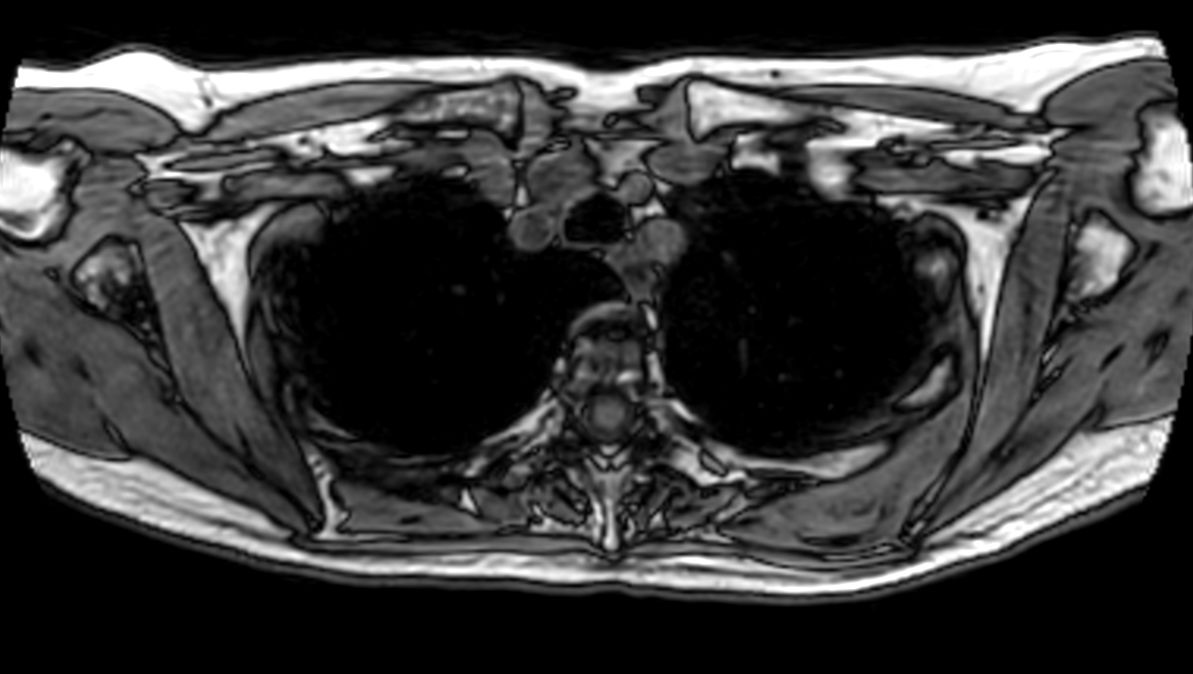

Patient with a thorax soft tissue lesion. ExamCard includes Compressed SENSE to shorten the scan time, MultiVane XD to acquire motion-free diagnostic images, 3D VANE XD helping to reduce motion artifacts during free breathing and 4D FreeBreathing to perform multi-phase contrast-enhanced MRI studies.

T2w TSE MultiVane XD - Free Breathing